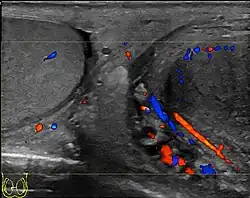

Doppler ultrasound of the scrotum, in the axial plane, showing orchitis (as part of epididymo-orchitis) as hypoechogenic and slightly heterogenic left testicular tissue (right in image), with an increased blood flow. There is also swelling of peritesticular tissue.